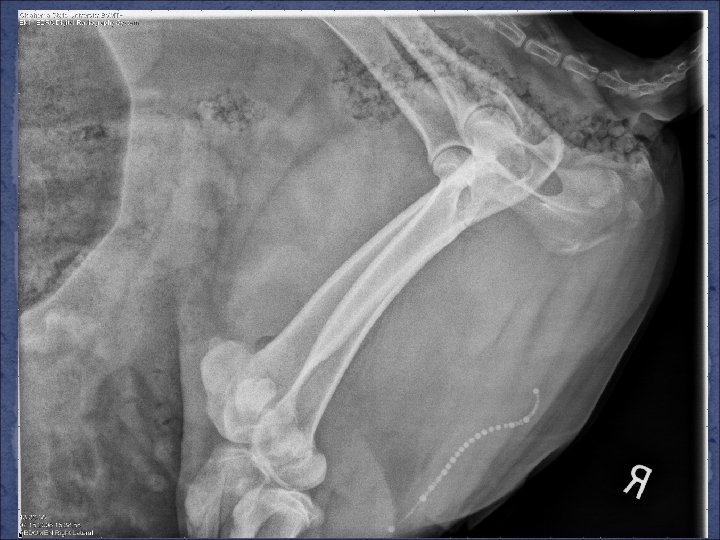

Diagnosis �Species, gender, history, clinical signs �Physical examination �Analysis of urine �IF possible…. incomplete obstruction or cystocentesis �Type of crystals/stones �Ultrasound �Urethra, bladder, kidneys, abdomen �Radiographs (x-rays) �Endoscopy